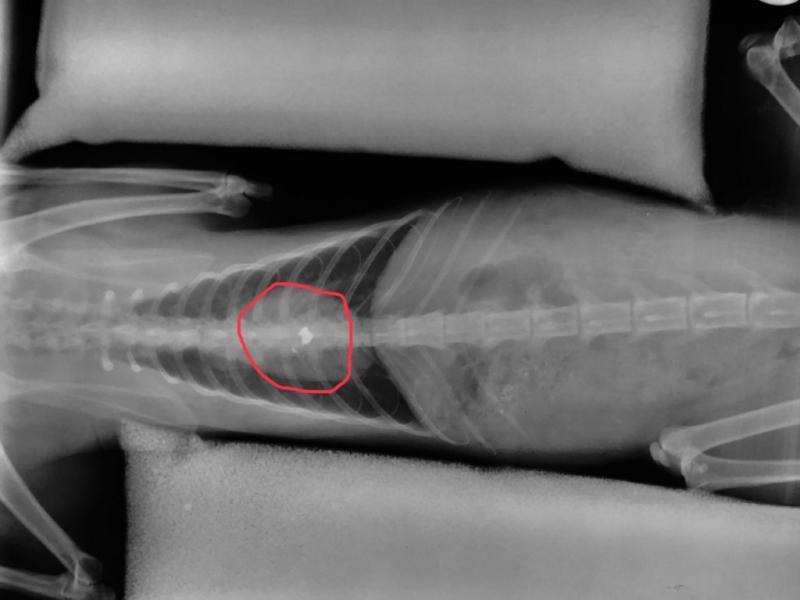

15.07.2019 - 07:29 Πέθανε ο γατούλης που πυροβολήθηκε από τον λυκειάρχη… Δεν άντεξε ο γατούλης που πυροβολήθηκε από εκπαιδευτικό σε χωριό του Δήμου Λαμιέων τα προηγούμενα 24ωρα. Ο εκπαιδευτικός αρνείται πως πυροβόλησε τη... ΚΟΙΝΩΝΙΑ Πέθανε ο γατούλης που πυροβολήθηκε από τον λυκειάρχη…